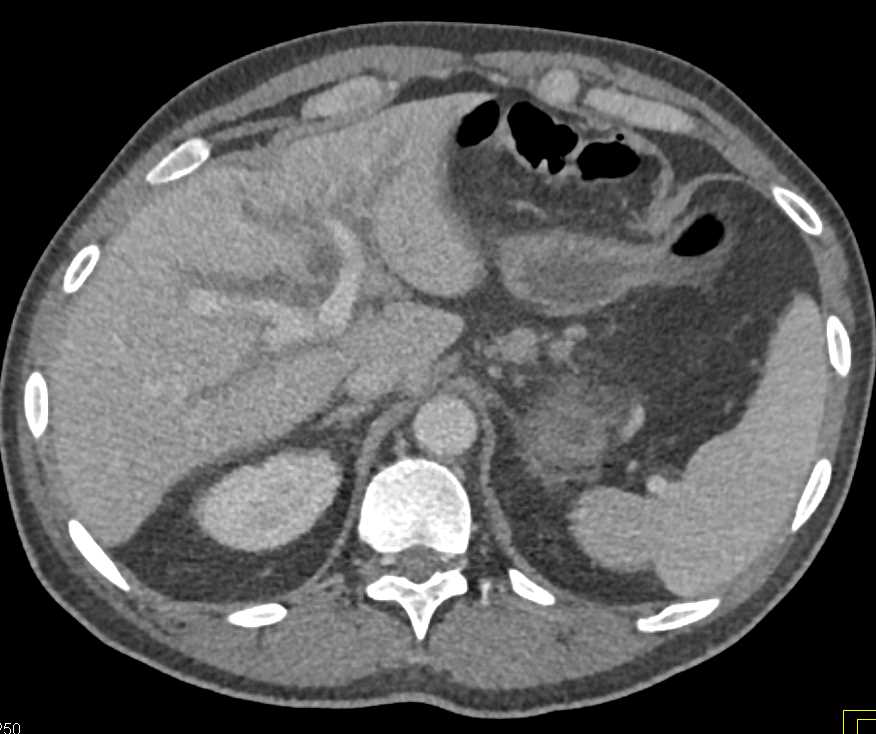

Recurrent Gastric Cancer with Liver Metastases